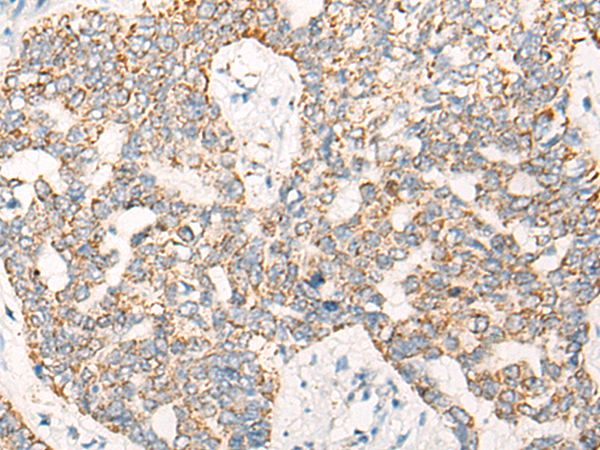

分类: 科研抗体货号: P00764别名: TRKB; trk-B; GP145-TrkB应用: IHC反应种属: Human, Mouse, Rat